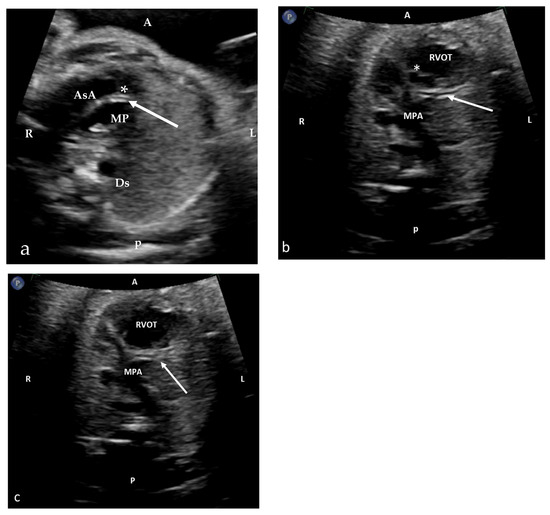

Figure 1. Salient prenatal imaging findings for Patients A and B. Fetal echocardiographic images at the high level of the RVOT (right ventricular outflow tract) of Patient A (a) and Patient B (b,c) at 29 and 5/7 and at 35 and 5/7 weeks’ gestational age, respectively. A coronary artery (arrow) is seen, coursing between the aorta and pulmonary artery and eventually following the anticipated course of the left coronary artery (LCA). Tip of arrow in image (c) points to the LCA bifurcation. * Aortic valve, AsAo = ascending aorta, MPA main pulmonary artery, DsAo = descending aorta. A = anterior, P = posterior, R = right, L = left.